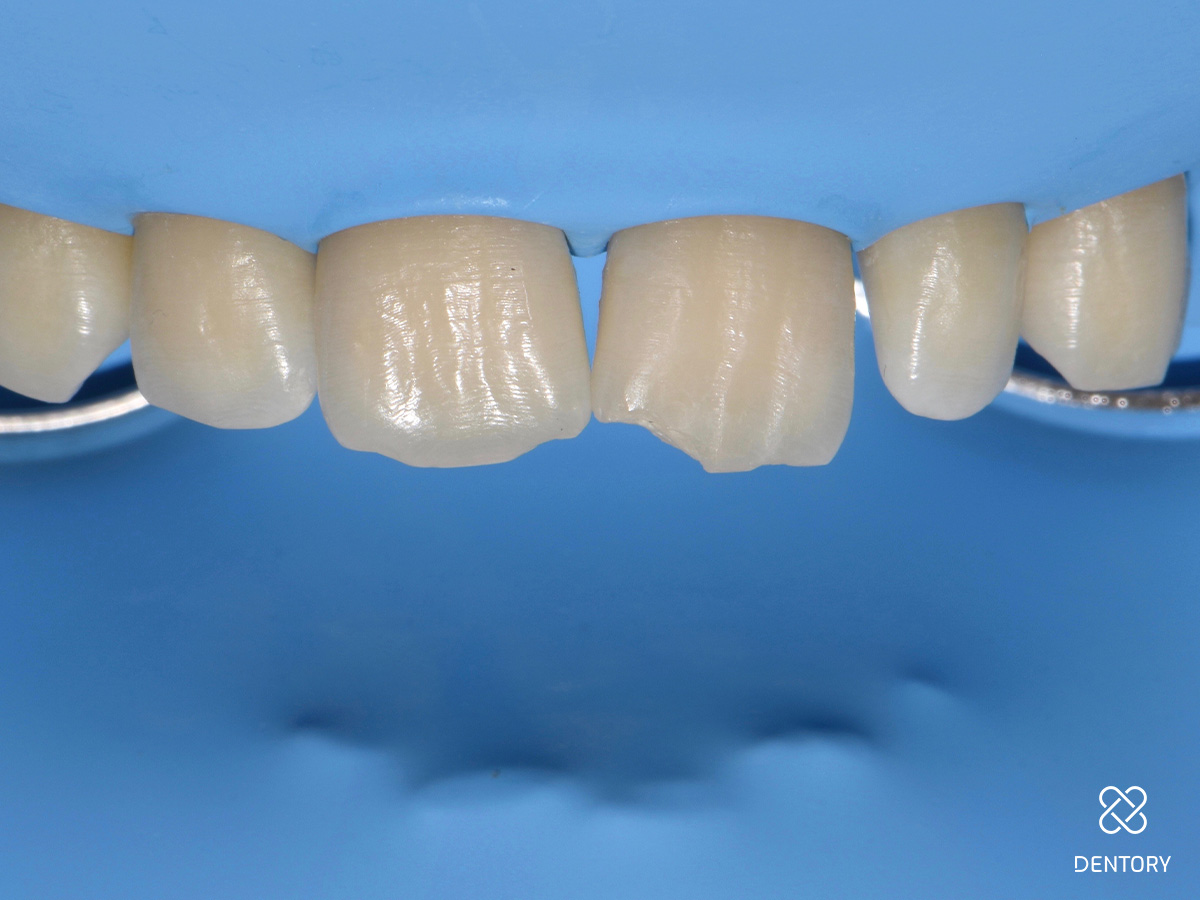

Abbildung 1

Farbbestimmung: Für die Farbauswahl werden Komposit-Proben direkt auf den Zahn platziert und ausgehärtet. In diesem Fall wurden A2 (o.r.) und Enamel Light (EL, u.r.) gewählt.